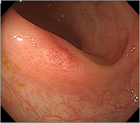

1. 患者背景、臨床症状からCMV腸炎を疑う場合は、組織採取が行える内視鏡検査が勧められる(推奨度1)

1. CMV腸炎診断のための内視鏡検査は、深部大腸まで観察し、潰瘍だけでなく、びらん、発赤、などの粘膜変化からも生検することが勧められる(推奨度2)